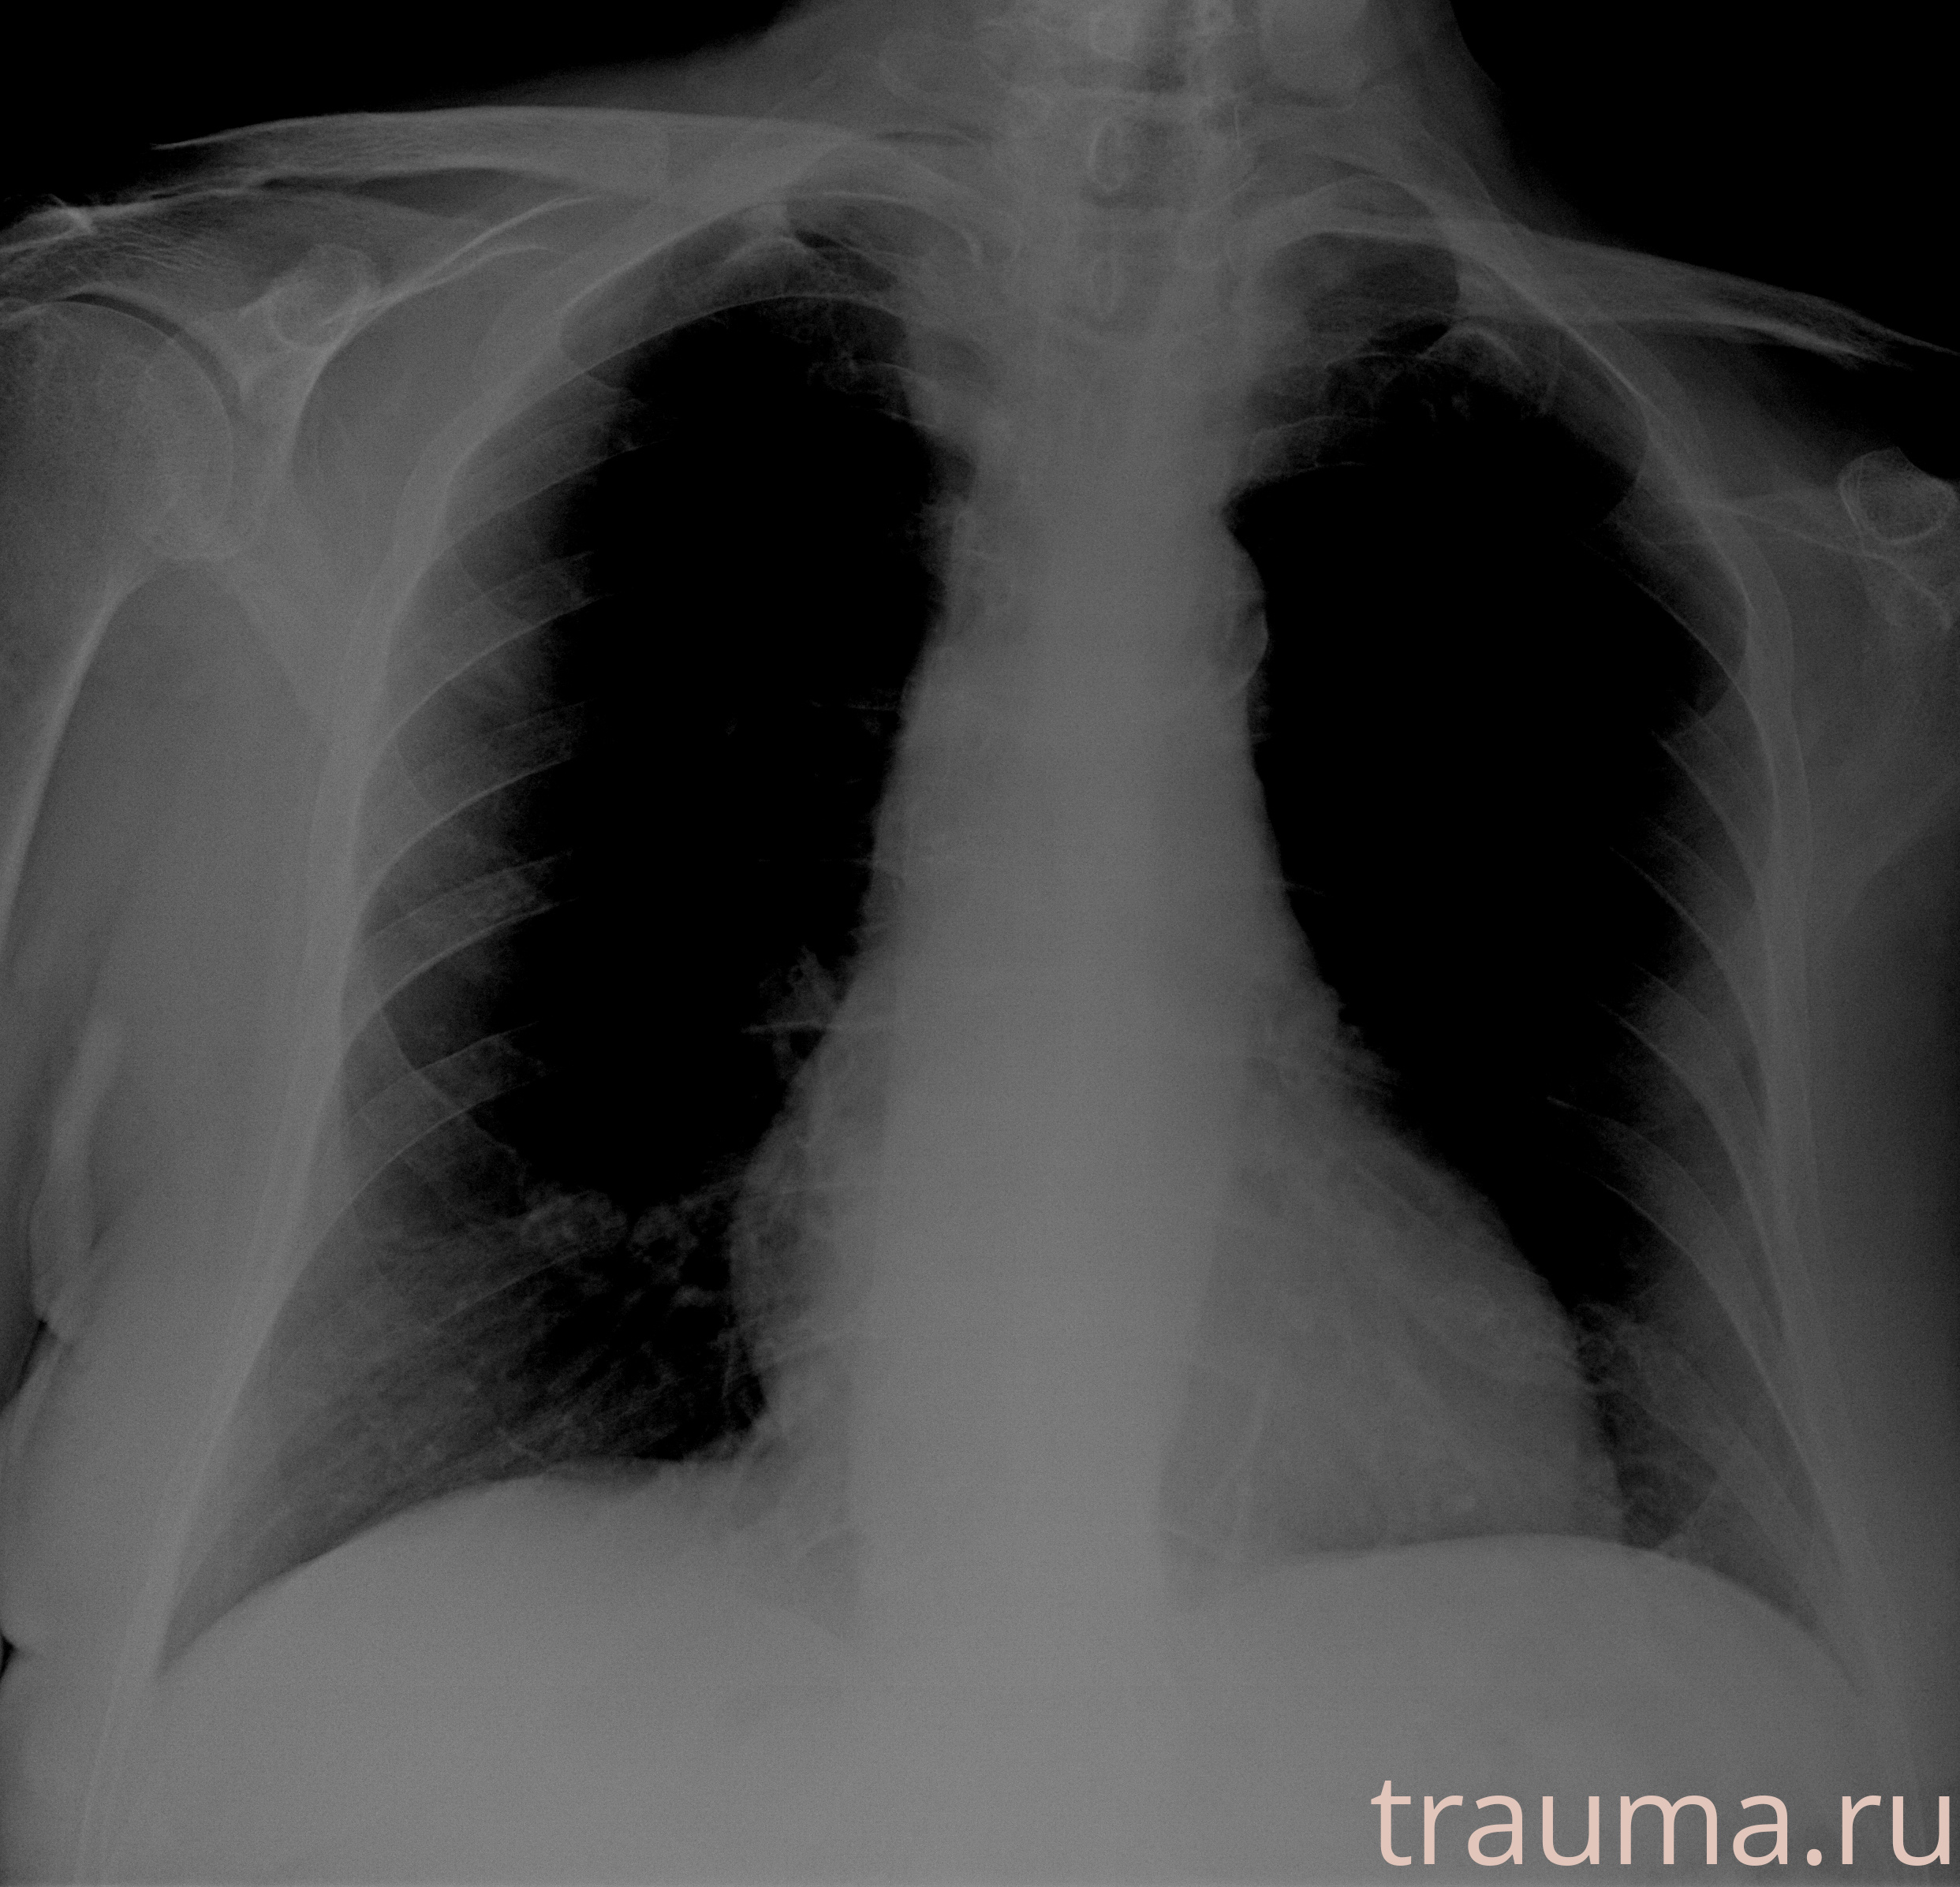

Рентгенограммы

Рентген на дому: по вашему адресу приезжает врач-рентгенолог, травматолог-ортопед с мобильным рентгеновским аппаратом, проводит диагностику травмы или заболевания, делает необходимые рентгенограммы, дает рекомендации по дальнейшему лечению. Получить качественные снимки в домашних условиях возможно благодаря уникальной методике, разработанной МосРентген Центром для института  Склифосовского

при переломе шейки бедра и пневмонии от компании МосРентген Центр - партнера Института имени Склифосовского